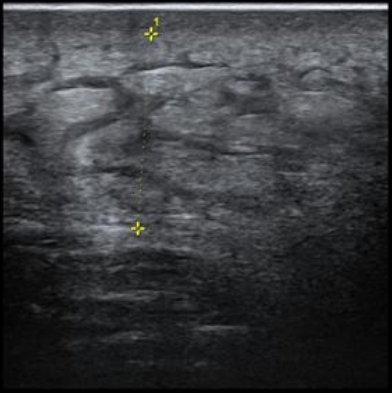

肛肠外科团队很快为杨先生安排了“复杂性高位肛周脓肿切口引流+高位肛瘘挂线术”。手术中发现,患者的脓腔范围达到13×6厘米,位置深且复杂,波及会阴部多个区域,筋膜组织已出现坏死。肛肠科团队精准地在三个关键点位建立引流通道,仔细清除坏死组织,反复冲洗脓腔。

然而,手术的成功只是康复的第一步。术后换药的效果将直接关系到治疗效果,而这个过程对患者而言却是巨大的考验。胡传恩医生深知这一点,在术后最关键的前几天,他坚持亲自为患者换药。每次换药都需要二十分钟,医生小心翼翼地清理创面,仔细冲洗脓腔,确保每一处坏死组织都被清除干净。这个拳头大小的脓腔,在胡医生日复一日的精心护理下,逐渐愈合,最终完全恢复。